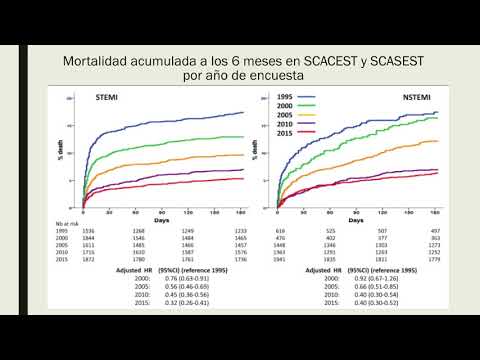

Infarto de Miocardio: registro FAST-MI. Dra. María Laura Estrella. Residencia de Cardiología. Hospital C. Argerich. Buenos Aires

Registro francés de IAM. Dr. Guido Vannoni. Residencia de Cardiología. Hospital C. Argerich. Buenos Aires